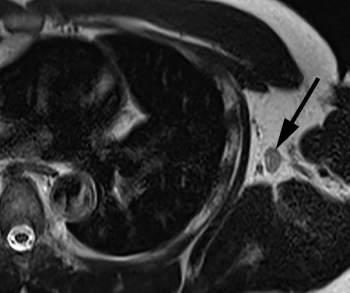

In a recent lecture at the Radiological Society of North America (RSNA) conference, Wendy DeMartini, MD, discussed a variety of preliminary proposed changes to the Breast Imaging Reporting and Data System (BI-RADS) for breast magnetic resonance imaging (MRI) examinations.